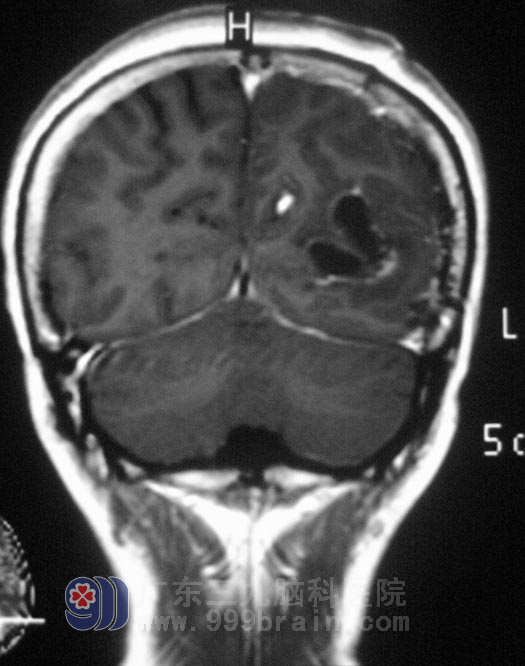

9月19日,由鲁明主任主刀,在全麻下行左侧顶枕部占位切除术,术中见肿瘤表面淡黄色,质软,血供一般,在显微镜下电凝完整切除肿瘤。术后病理为:(左顶枕叶)节细胞胶质瘤,WHO I级。经过进一步的治疗,温女士康复出院。

▲手术后